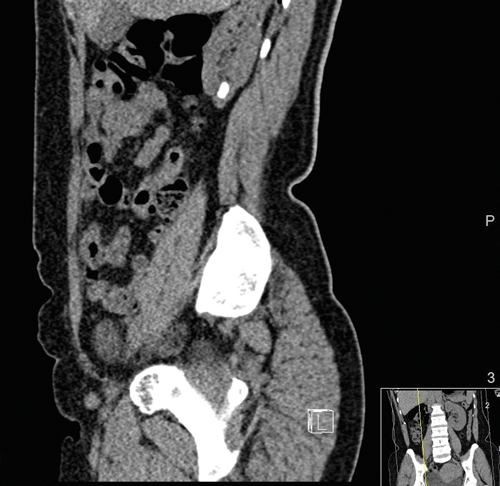

Figure 1a and b: CT images revealing the calyceal diverticular stone.

The mainstay of imaging is computed tomography kidneys, ureter and bladder (CTKUB) with pre and post contrast images (Figure 1). Pre-contrast imaging will enable detection of calculi and gross anatomical variations. Using contrast, an early phase calyceal diverticulum will appear as rounded a low attenuation area next to the calyces. The delayed contrast (excretory) phase will show filing of this area with minimal overlying cortex [17]. Differential diagnoses such as hydrocalyx, simple cysts, parapelvic cysts, tubercular cavity, papillary necrosis and renal tumours may be detected. The CT is vital for surgical planning as three-dimensional reconstruction can be undertaken to help plan the puncture for the percutaneous approach.